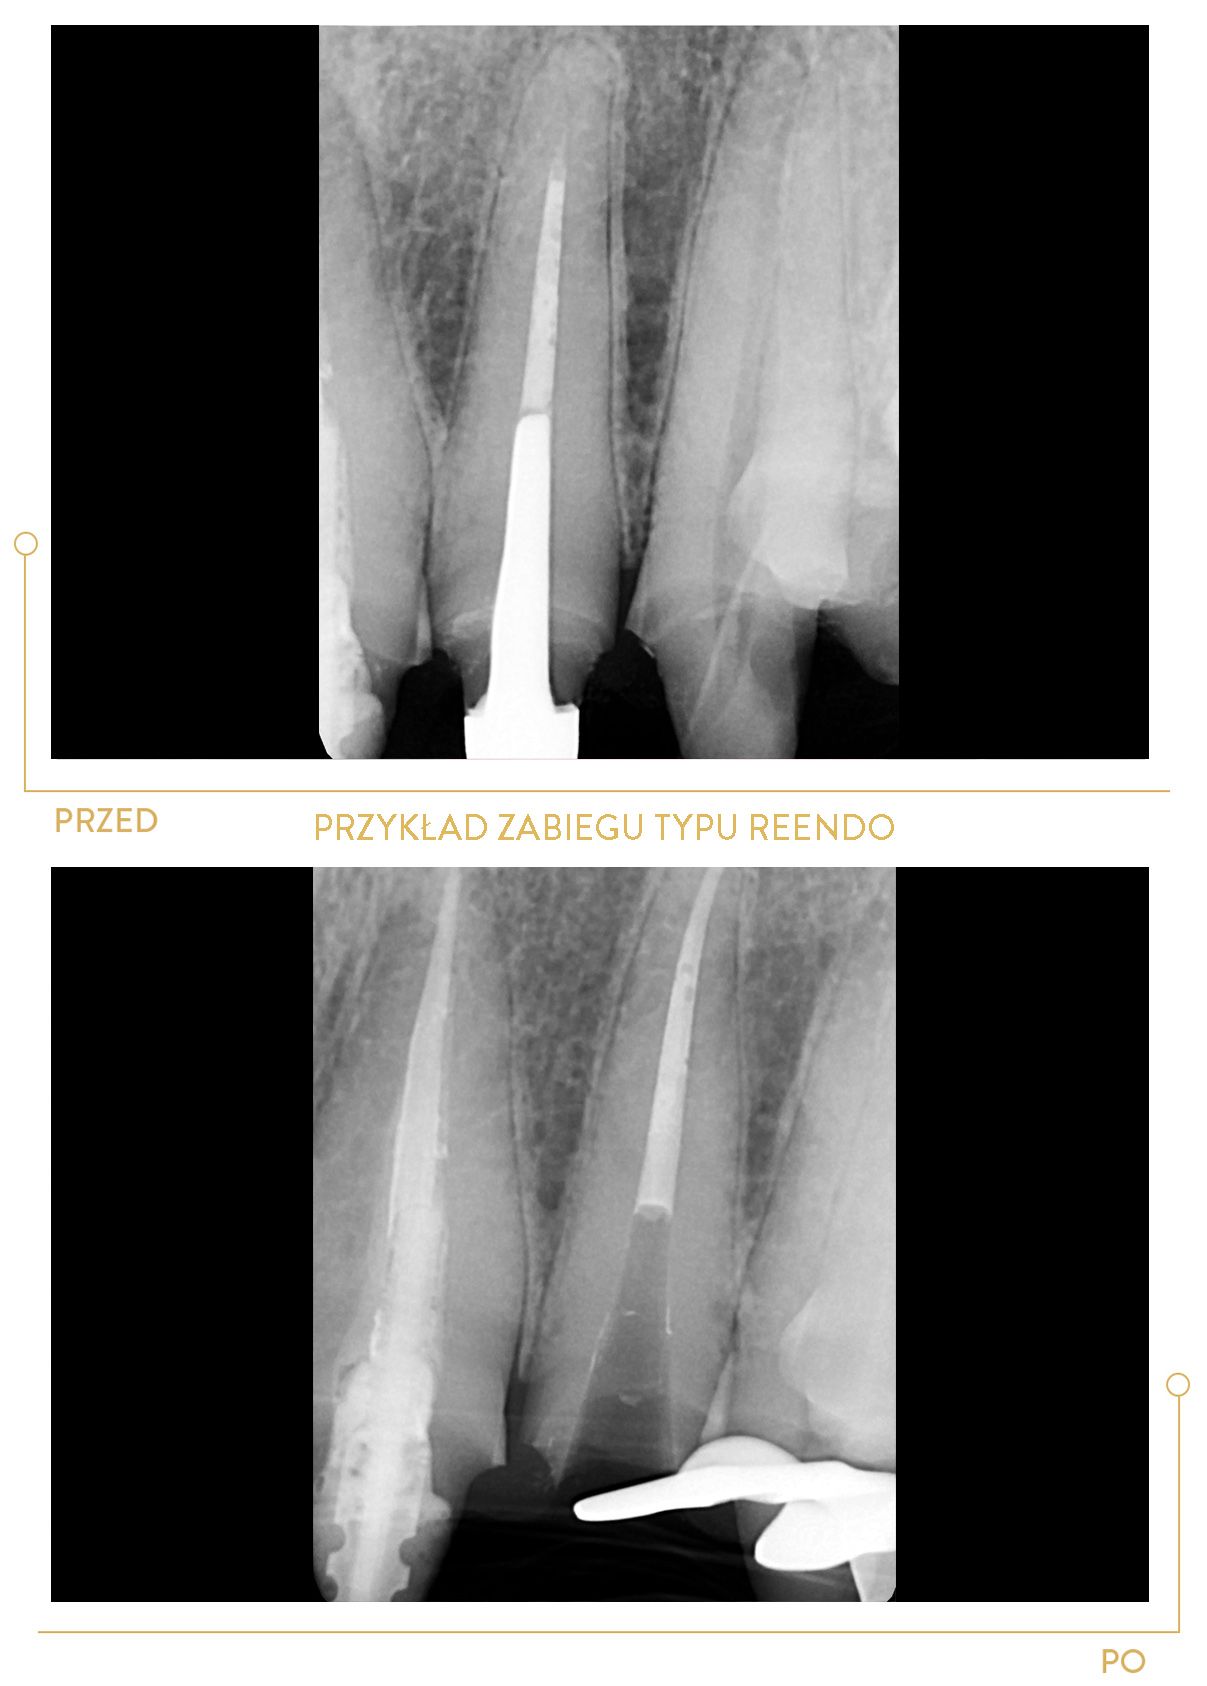

Dzięki ciągłemu rozwojowi zawodowemu do jej kompetencji należy również nowoczesne leczenie endodontyczne pod mikroskopem. W Centrum Stomatologii Cichoń realizuje swoje pasje zawodowe, szczególnie w obszarach:

Duża ambicja, ciekawość i zaangażowanie sprawiają, że dąży do pogłębiania wiedzy w wielu dziedzinach stomatologii, ze szczególnym uwzględnieniem endodoncji.

Doktor Magda Grabowska to lekarz o wielkim doświadczeniu. Była moją ostatnią nadzieją jeżeli chodzi o uratowanie mojego zęba. Była to 3 więc tym bardziej jestem jej wdzięczny. Ząb przeleczony kanałowo pod mikroskopem z pełną precyzją. Pani doktor bardzo dziękuję!

Doktor Magda jest niewątpliwie najlepszym specjalistą w leczeniu kanałowym. Ząb którego żaden z lekarzy nie był w stanie udrożnić pani doktor wykonała powtórne leczenie kanałowe na jednej 1,5 godzinnej wizycie które zakończyło się odbudowa estetyczna . Po ogromnych zmianach zapalnych nie ma śladu . Dziękuje z całego serca .

Dr Magda uratowała mojego bolącego zęba przeznaczonego do usunięcia... Jej spokój i profesjonalizm i dokładność po prostu mnie powaliły. Nie wiem jak to jest, że w jednym miejscu każą zęba usunąć, a w innym okazuje się, że da się go uratować. Po wizycie miałam porównanie - chodzi o wiedzę i doświadczenie. Dr Magda to definitywnie lekarz godny polecenia, szczególnie do ciężkich przypadków.